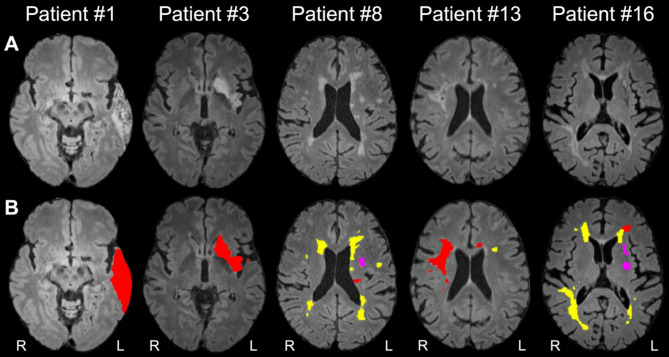

Results: [18F]FEPPA-PET, DTI, and T2-weighted FLAIR were acquired at 6-months post-stroke in 19 elderly humans (seven females; mean age = 76 ± 5 years) with confirmed first-ever acute ischemic stroke using hybrid PET/3T-MRI. Index infarcts, chronic (incidental, covert) infarcts, and WM hyperintensities were manually segmented on FLAIR and excluded from the imaging analysis. Pearson correlation was conducted to assess the association between [18F]FEPPA-SUVr and DTI measurements in WM regions commonly implicated in PSCI. [18F]FEPPA-SUVr was elevated in brain regions ipsilateral to the index infarct at 6-months post-stroke, and these increases correlated with decreases in fractional anisotropy in several WM pathways linked to PSCI, including right superior longitudinal fasciculus (SLF) III (r = -0.82, p < 0.0001), right anterior thalamic radiation (r = -0.61, p = 0.006), and right arcuate fasciculus (r = -0.56, p = 0.01). Elevated [18F]FEPPA-SUVr was also associated with increased mean diffusivity (r = 0.69, p < 0.001), axial diffusivity (r = 0.55, p = 0.02), and radial diffusivity (r = 0.74, p < 0.001) in right SLF III.

Conclusions: This study found an association between elevated post-acute glial activation (neuroinflammation) and reduced microstructure integrity in brain WM pathways ipsilateral to ischemic infarcts and remote from WM lesions at 6-months post-stroke. Hybrid PET/MRI is promising to be a valuable tool for probing post-acute neuroinflammation and associated changes in cerebral WM pathways following ischemic stroke.